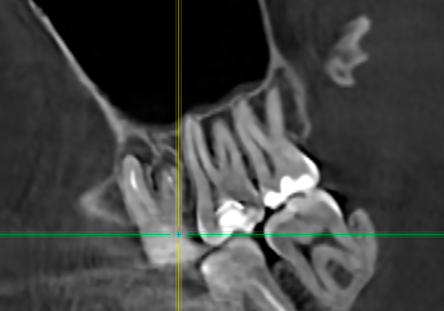

>>1636864

а как бяка может долго там сидеть, если ты ежедневно очищаешь? Другое дело капюшон у зуба, куда еда забивается - оно там просто гниет, но это не кариес. Но гнилостный тухлый запах - обычно проблема с зубом (пульпит, кариес, болезнь десны). Как вариант еще камень может быть.

Еще вариант - киста, она тоже может давать боль между зубами, хотя может казаться, что порезал десну.

Тебе снимок КТ делали или обычный черно-белый? На КТ и кариес виден (но могут быть погрешности) и киста

>>1636970

Обычный рентген.

Но у меня не как пикрил.

У меня восьмерка. Последний зуб. Соседняя семерка в норме. Т.к. чищу под кожей над восьмым зубом сверху